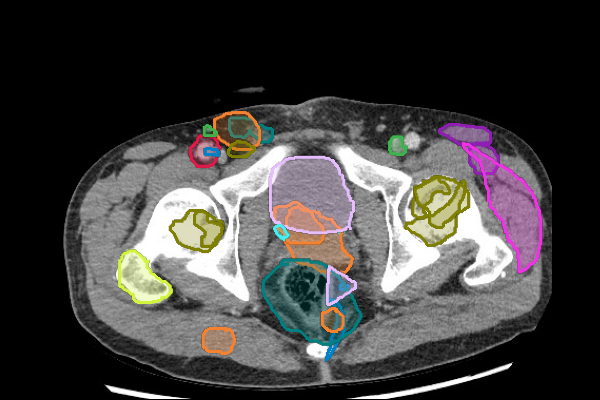

Legend

Slice 1

Slice 2

Slice 3

Slice 4

Slice 5

Slice 6

Slice 7

Slice 8

Slice 9

Slice 10

Slice 11

Slice 12